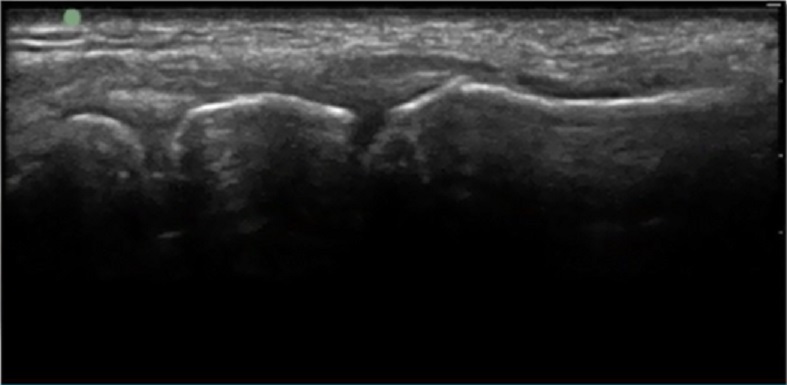

手首の第1CMC関節注射解剖2の画像